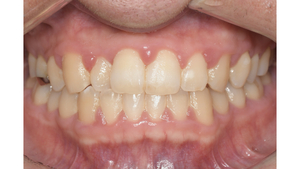

健康な歯ぐきの特徴

健康な歯ぐきは、綺麗なサーモンピンク色で、歯と歯の間が三角形でうまっています。近くで見ると、表面にみかんの皮のような細かなつぶつぶがあります。痛くない程度の力で歯ブラシの毛先を歯ぐきに当てて磨いてみましょう。出血が起こらなければ、健康な状態だといえます。

健康な状態の歯ぐきの写真